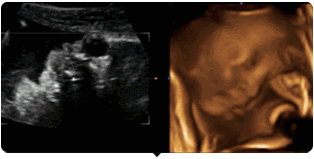

彩超其实还是黑白的,而三维、四维彩超在做出三维、四维图像的时候才是土黄色,也并非彩超就是色彩斑斓的。

被称为彩超,是因为会用彩色标注心脏、血流等指标。彩超的分辨率会比一般黑白B超高一些。而因为能用彩色标注血流,当脐带绕颈的时候就会看见宝宝的脖子上呈U形或者W形的血流,对是否脐带绕颈也就一目了然了。

四维彩超能够多方位、多角度地观察胎宝宝在宫内的实际生长发育情况,为早期诊断胎儿先天性体表畸形和先天性心脏病等提供准确的科学依据。

通过四维彩超可以看到宝宝的表情动作,更为重要的是,它能够多方位、多角度地观察宫内胎儿的生长发育情况,为早期诊断胎儿先天性体表畸形和先天性心脏疾病提供准确的科学依据。

第1大亮点

盐城艾琪儿妇产医院引进的美国GE-E8四维彩超,是目前最先进的彩色超声设备,被誉为“神奇彩超”,能360°立体展现胎儿各器官的发育情况,是应用于胎儿产前排查畸形及缺陷儿的终极诊断,并完整纪录胎儿宫内高清动态的尖端设备,它用出色的人体工程学设计,不存在电离辐射和电磁辐射,对人体组织没有任何影响,而且医学使用的超声属于低强度,低于94毫瓦/立方厘米,对胎儿没有任何危害,所以准妈们可以放心进行孕检,不用再担心是否会有损宝宝的健康